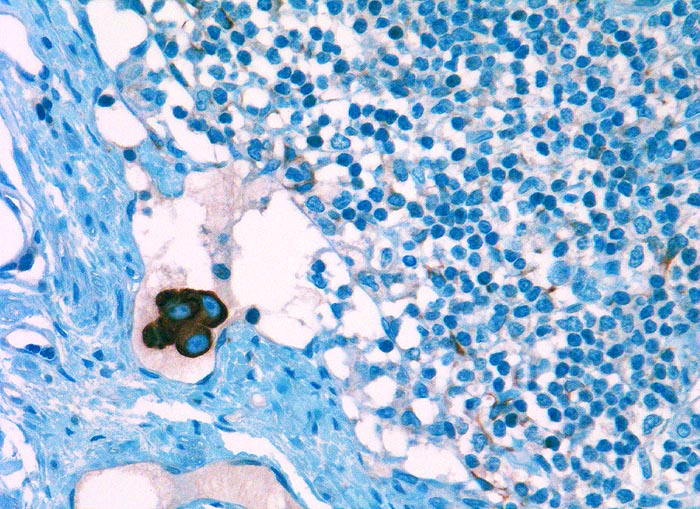

Diagnostischer Nutzen:

Suchantikörper zur Abgrenzung von Karzinomen von Lymphomen, Sarkomen und malignen Melanomen. Identifikation von Karzinommikrometastasen in Lymphknoten.